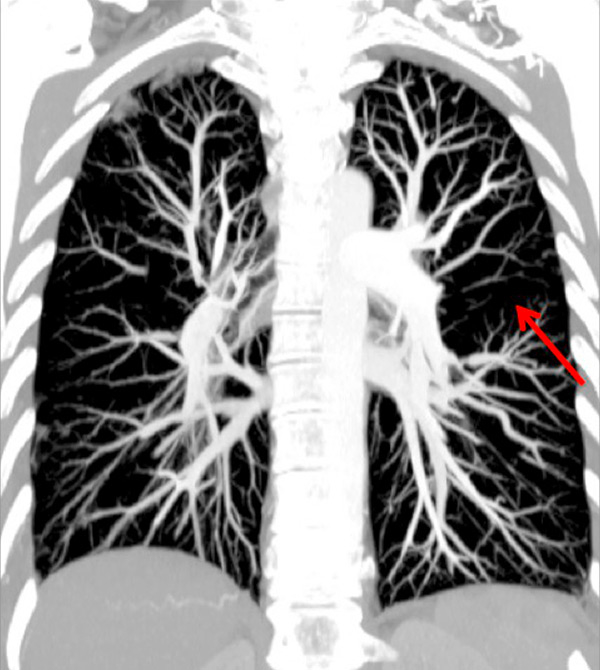

Figure 2

Chronic thromboembolic pulmonary hypertension (CTEPH). Vascular (A) and parenchymal (B) signs of CTEPH with proximal marginal occlusion (arrows) and mosaic pattern (stars). Functional information simply added with triangular perfusion defects (stars) on the iodine maps (C).